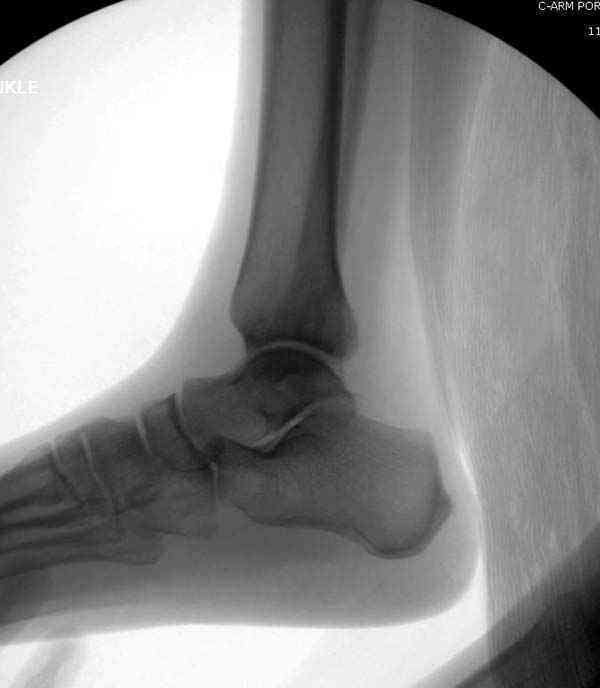

Случай прошлого года:пациентка-молодая ,крупная женщина ,30лет.Травма в начале апреля 2009г-пронационный перелом лодыжек с подвывихом стопы.Ко мне обратилась через 35 дней,прооперирована 22.05.2009г.Внутренняя лодыжка фиксирована по Веберу,наружная реконструктивной пластиной с наложением болта-стяжки.Иммобилизация "сапожок" в течении месяца,затем пригипсовано "стремя".Гипс снят 10.07.2009г

Достаточно быстрое восстановление функции.В октябре 2009г-почувствовала боль,в области рубца над гайкой открылся свищ.На Р-граммах-консолидация переломов и смещение гайки по стяжке.10.11.2009г-конструкции удалены,санация,заживление ран.В настоящее время пациентку ничего не беспокоит.На операции-раскручивание гайки-болталась на конце стяжки.Вопросы:какой механизм раскручивания и что я неправильно сделал?Свои версии:1)в области синдесмоза успела образоваться рубцовая ткань,которая при движении в суставе"пружинила",поскольку голеностопный сустав является спиральным, то и биомеханика подобна кривошипному механизму.2)Реконструктивная пластина не "реконструировалась" по форме лодыжки.Наложил,как есть.То есть подпружинивала сама пластина.Ну,это мои догадки.Что нужно,чтобы избегать впредь таких,пусть и не "страшных"осложнений:Рассверливать через лодыжку область синдесмоза?Ставить шайбу-гровер?Тщательно моделировать пластину?Прилагаю сравнительные снимки-сразу после операции и перед удалением конструкции.

Визуально никаких вопросов по репозиции не было.Да и на основании чего сомнения,что наружная лодыжка не полностью репонирована или прорезалась проволка ???Я не вижу...Снимок после репозиции справа.